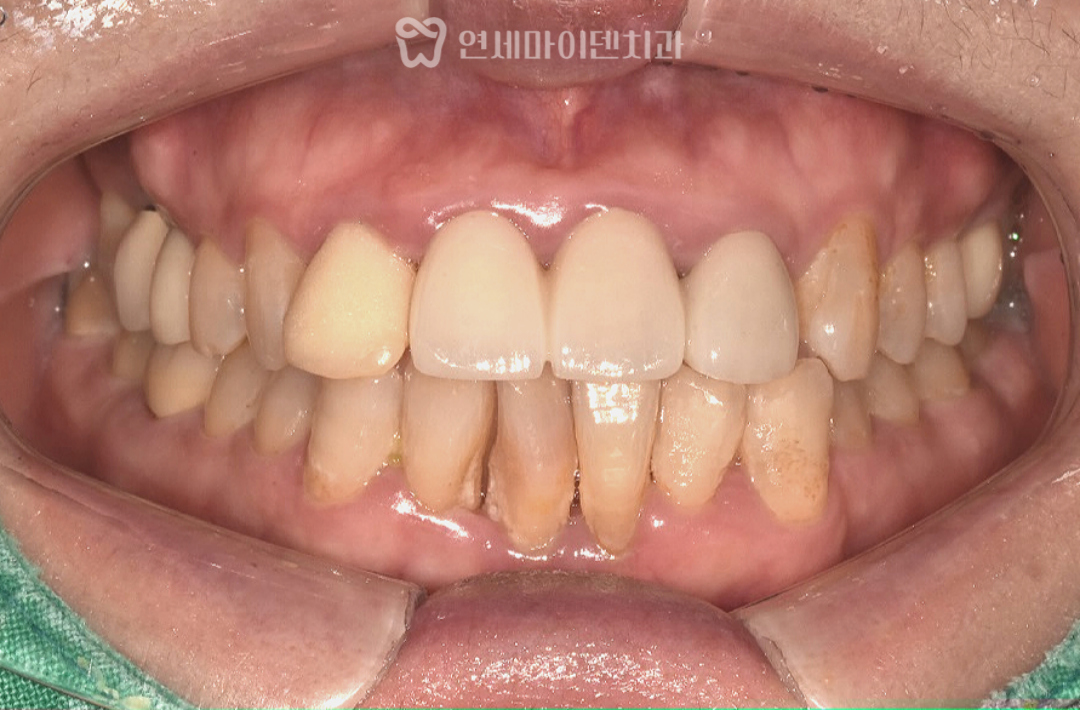

초기 진단에서 확인된 상태

중장년층 환자분들은 이미 과거에

보철 치료를 받아본 경험이 있는 경우가 많습니다.

이번 사례에서도 윗앞니 일부가

보철물로 연결되어 있었고,

아래 앞니는 배열이 고르지 못한 상태였습니다.

시간이 지나면서 기존 보철물의 심미성이 떨어졌고,

과거 교정 이후 다시 치아 사이에 틈이 생긴 점이

불편함으로 이어져 치료를 결정하게 되었습니다.

단순히 치아 배열만의 문제가 아니라,

기존 보철 상태와 현재의 교합 관계를

함께 살펴봐야 하는 상황이었습니다.

3급 부정교합의 특징과 잇몸 상태

검사 과정에서 치석이 많이 쌓여 있고,

잇몸이 전반적으로 부어 있으며

잇몸뼈가 내려간 소견이 확인되었습니다.

일부 치아 뿌리 끝에는

염증 소견도 동반되어 있었습니다.

방사선 사진에서는 윗턱보다 아래턱이

상대적으로 발달한 3급 부정교합(주걱턱) 이었고,

위턱 앞니는 앞으로 뻐드러진 상태였습니다.

이러한 골격적·치성적 특징은 치아 배열뿐 아니라

전체 교합 관계에도 영향을 주고 있었습니다.